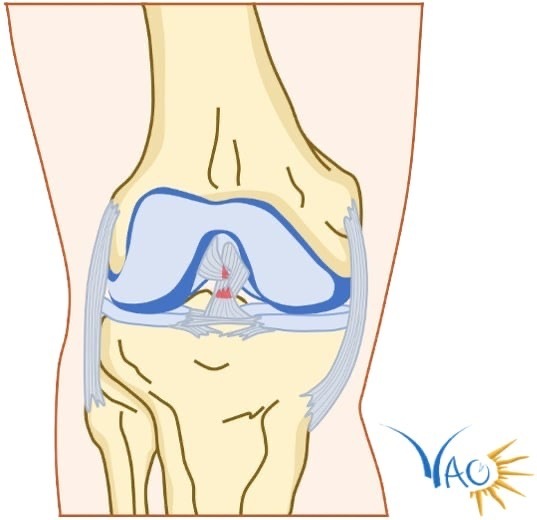

Le genou est une articulation complexe située entre le fémur, le tibia et la rotule, stabilisée par quatre ligaments majeurs : deux ligaments collatéraux (un médial et un latéral) et deux ligaments croisés qui constituent le pivot central (un antérieur et un postérieur) [fig. 1]. Le ligament croisé antérieur est une bande de tissu conjonctif fibreux, blanchâtre, très résistant, situé à l’intérieur du genou, tendu du fémur jusqu’au tibia.2 Il a pour rôle principal de contrôler la translation antérieure du tibia par rapport au fémur et d’assurer la stabilité rotatoire du genou. Le LCA est classiquement décrit comme un ruban torsadé composé de deux faisceaux : un faisceau principal antéromédial et un faisceau moins épais postérolatéral. C’est la raison pour laquelle une rupture partielle du LCA avec préservation des fibres du faisceau postérolatéral est parfois évoquée.